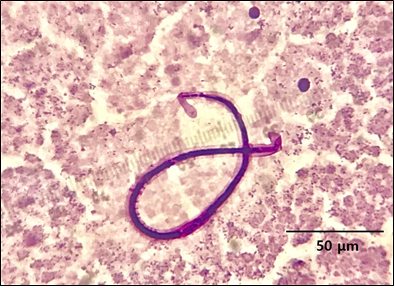

35세 남자가 2주 전부터 열이 나고 피곤하다고 병원에 왔다. 인도네시아 밀림지역에서 1년 동안 근무하다가 1개월 전 귀국했다고 한다. 신체검사에서 겨드랑이 부위의 림프절이 부어있다. 혈액을 김사염색한 결과이다. 이 병원체에 수년 간 반복 감염되었을 경우 발생할 수 있는 후유증은?

• 절지동물에 의해 매개되는 사상충은 사상충증을 일으킨다. 그 중에서 성충이 사람의 림프계에 살며 번식하는 사상충증을 림프사상충증이라 하는데, 대표적인 원인으로 반크롭트사상충과 말레이사상충이 있다. 반크롭트사상충의 증상이 전반적으로 더 심하다.

• 발이 코끼리 다리와 같이 되는 상피증이 대표적인 증상이며, 면역반응에 의해 일어나 기생충을 제거하여도 치료되지 않는다. 또한 발열, 손발 부종, 근육통, 림프관염, 림프선염, 음낭수종 등이 나타날 수 있다. 성장하는 데에 시간이 걸려 증상이 늦게 나타나는 탓에 인과관계를 찾기 어렵다.

• 성충이 낳은 미세사상충은 혈액 내에 존재하는데, 특이한 점은 림프사상충의 경우 정기출현성을 지닌다는 것이다. 낮에는 심장 등 중심부에 존재하다가, 모기가 피를 빠는 밤에는 말초혈액으로 이동하게 된다. 자정에 최고조를 이룬다.